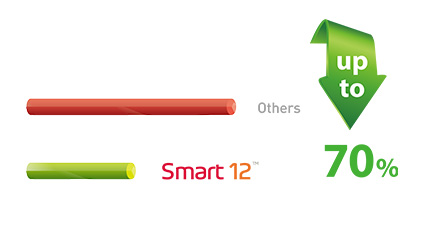

低剂量,高清影像

vatech开发的技术打破了牙科射线照相技术的许多惯例。 人们一直认为,低辐射带来的图像质量较差,这使得它在临床诊断中毫无用处。 然而,Smart 12在低X射线剂量下提供临床可诊断的X射线扫描。 使用低剂量放射照相技术,实现临床可诊断的图像质量是新的黄金标准。